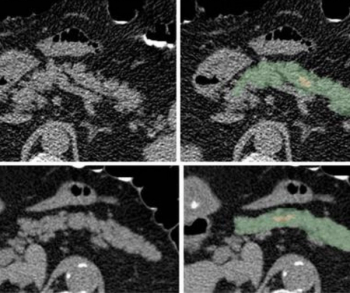

Employing a deep learning system for pancreatic segmentation, researchers found that intrapancreatic fat percentage and pancreatic fractal dimension were among the key predictors for type 2 diabetes mellitus in a multivariable analysis.